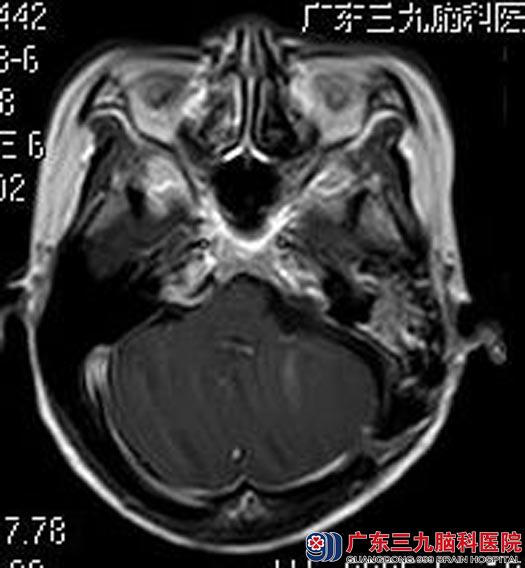

术后区女士声音嘶哑、吞咽困难较前好转,无面瘫等术后并发症,康复出院。术后病理结果:神经鞘瘤。

▲手术后